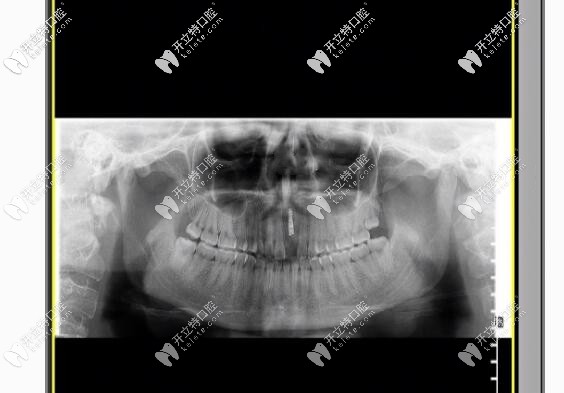

拍片圖示

幸好我找對(duì)了醫(yī)院和醫(yī)生,醫(yī)生給我的建議是拆除烤瓷牙,換上瑞士iti或瑞典nobel種植牙,幾番考慮之后,我選擇的是瑞士iti種植牙,有利于骨愈合,還不用進(jìn)行二期手術(shù)什么的,我給忘了,也正好趕上美奧口腔有活動(dòng),價(jià)格優(yōu)惠的狠喲!